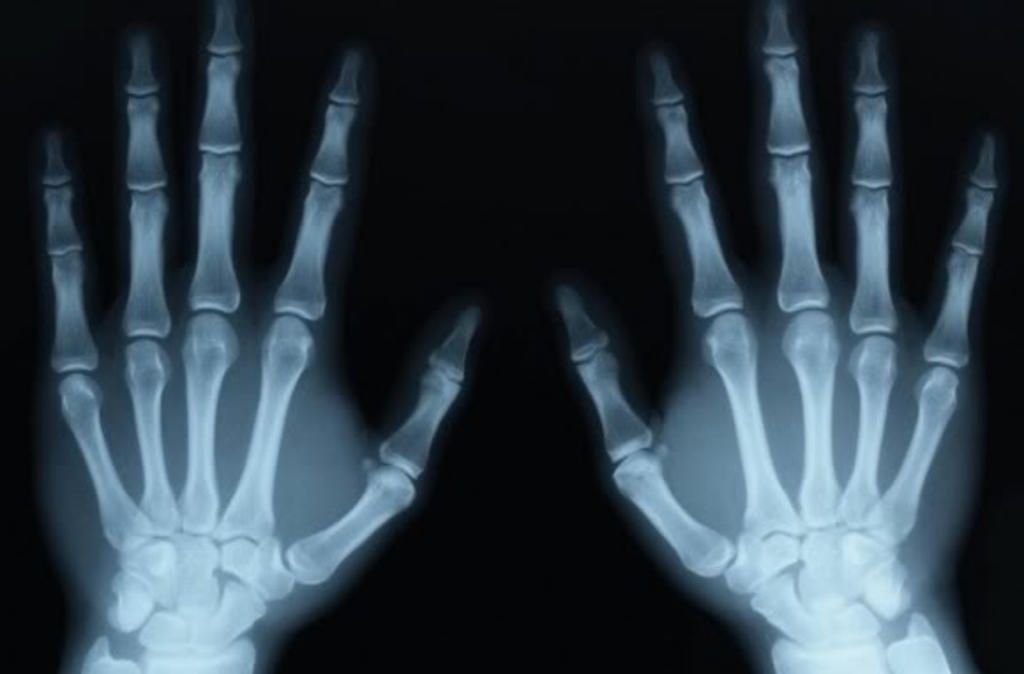

Ảnh 4: nhờ tìm ra chất phóng xạ radi, đó là nền tảng sau này để tạo ra các loại máy chiếu tia phóng xạ như tia X được sử dụng trong các máy X-quang ngày nay.